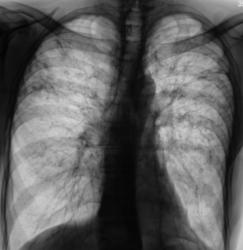

При расшифровке цифровых флюорограмм пациент был взят на контроль, дообследован - рентгенография, томография, был выставлен диагноз - "диссеминированный туберкулёз легких". В мокроте были выявлена МБТ. Пациент госпитализирован в ПТД.

Сегодня, пациент направлен на плановое обследование нашим фтизиатром. Оказывается, пациент выписан, после "курса лечения", под наблюдение фтизиатра "по месту жительства".

Ваше мнение коллеги по поводу "эффективности" проведенного лечения.

Впечатление о положительной динамике. Сохраняються плотные очаги.

А куда денешь 2 полости справа на уровне 2-3 ребер, и очаговые тени в верхних и средних полях с 2 сторон в фазе инфильтрации?

Насчёт полостей, на мой взгляд не убедительно; оценка плотности очагов, такие тонкие и принципиальные вопросы решаються не в интернете, а по снимкам с учётом R-архива, возможно с использованием дополнительных исследований( R-скопии и т.д.).  С увжением Морозов Александр.